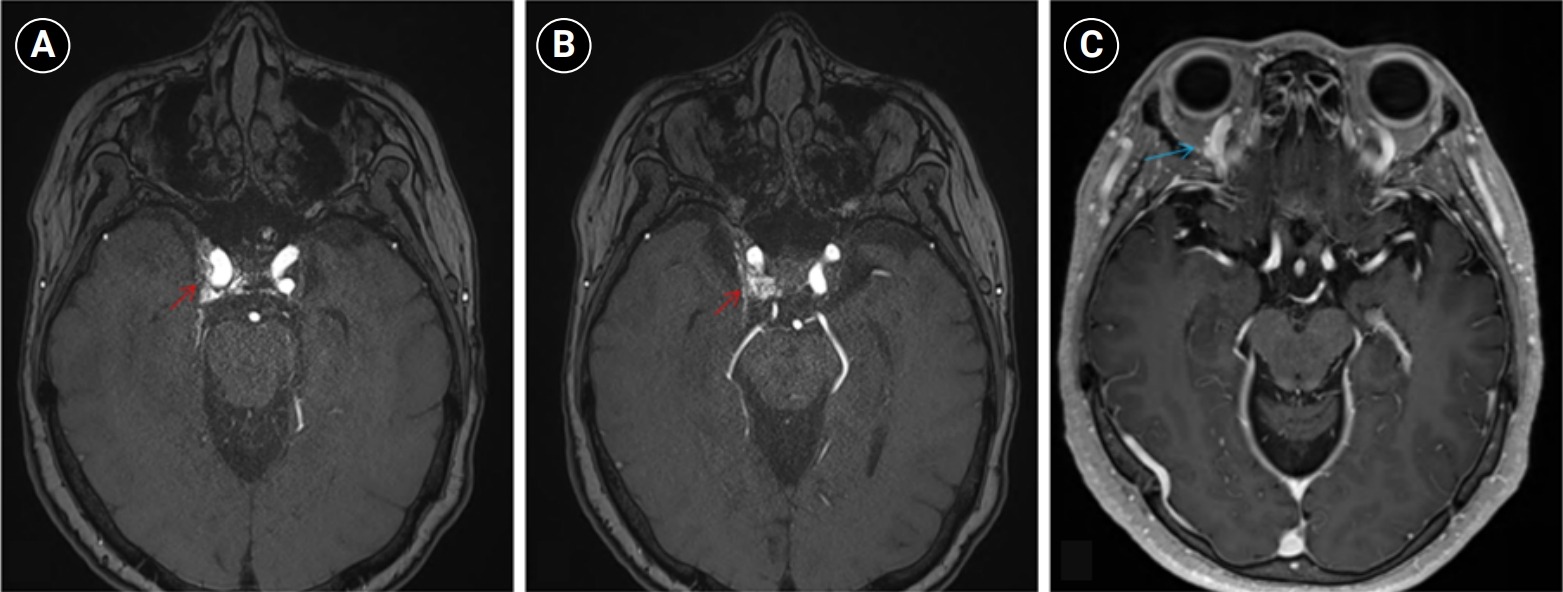

Baseline hematology and chemistry—including complete blood count, electrolytes, renal/hepatic indices—and coagulation tests (prothrombin time/international normalized ratio, activated partial thromboplastin time) were within reference limits. Erythrocyte sedimentation rate and C-reactive protein were normal. A focused screen for secondary trigeminal neuropathy (thyroid-stimulating hormone, vitamin B12, HbA1c) was negative. There were no clinical signs of infection. Brain magnetic resonance imaging (MRI) demonstrated high flow related signal in the right cavernous sinus and asymmetric dilation of the superior ophthalmic veins (right>left), raising suspicion for a CCF (Figure 1). Definitive diagnosis was established on digital subtraction angiography (DSA), which identified a right CCF. DSA demonstrated an indirect CCF supplied by the right meningohypophyseal trunk of the ICA and by right ECA branches, including the internal maxillary artery and the cavernous branch of the middle meningeal artery, consistent with Barrow type D (Figure 2).6 Barrow type D denotes an indirect, low-flow fistula with dual ICA/ECA dural supply; unlike direct type, indirect types present more insidiously, and symptom patterns are largely determined by venous drainage, with posterior drainage often manifesting as CN VI palsy and headache (Table 1).1,3,6,7 The fistula was treated with transvenous Onyx embolization. On post-procedure day 1, non-contrast time-of-flight magnetic resonance angiography (TOF-MRA) demonstrated a marked reduction of flow related hyperintensity within the right cavernous sinus, and the right superior ophthalmic vein caliber decreased from 6.63 to 4.61 mm (Figure 3A, B). Follow-up DSA (at 3 weeks) likewise showed substantial attenuation of fistulous opacification (Figure 3C), supporting a significant interval decrease in arteriovenous shunting. At 1–2 weeks, the patient reported an ~80%–90% reduction in dental/lower-facial pain and bifrontal headache from NRS 7–8 to 1–2. By 1 month, red-glass testing demonstrated resolution of primary-position diplopia. Formal prism measurements were unavailable; bedside ocular-motor grading was recorded using a standard duction underaction scale (–4 to 0). Right abduction improved from –1 to 0, and primary-position diplopia was absent at distance and near, consistent with recovery from abducens palsy.

Digital subtraction angiography findings in the patient. (A) Right internal carotid artery (ICA) angiogram shows an indirect carotid-cavernous fistula supplied by the meningohypophyseal trunk of the cavernous ICA (black arrow). (B, C) Right external carotid artery angiogram demonstrates additional arterial supply from external carotid branches, including the internal maxillary artery (blue arrows) and the cavernous branch of the middle meningeal artery (red arrows).